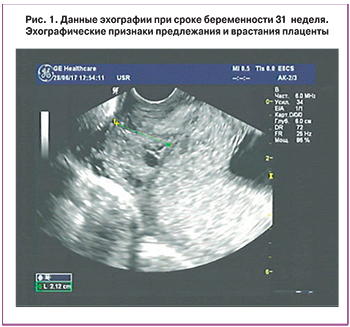

По данным УЗИ, проведенном в ККК ЦОМД при поступлении пациентки, было установлено, что фетометрические показатели соответствуют 31 недели беременности, плацента расположена на передней стенке матки и полностью перекрывает область внутреннего зева шейки матки. Кроме того, на основании данных допплерометрии было установлено наличие патологического хода сосудов между плацентой и стенками матки (передней и задней). Также определялось выраженное истончение миометрия в области нижнего сегмента матки – до 1 мм, то есть, были выявлены косвенные признаки врастания плаценты (рис. 1).

Область внутреннего зева шейки матки четко не визуализировалась и врачом, проводившим УЗИ, было сделано заключение о вероятности прорастания плаценты в цервикальный канал шейки матки. К сожалению, подтвердить факт врастания плаценты данными МРТ не удалось из-за выраженного синдрома «нижней полой вены» у пациентки.